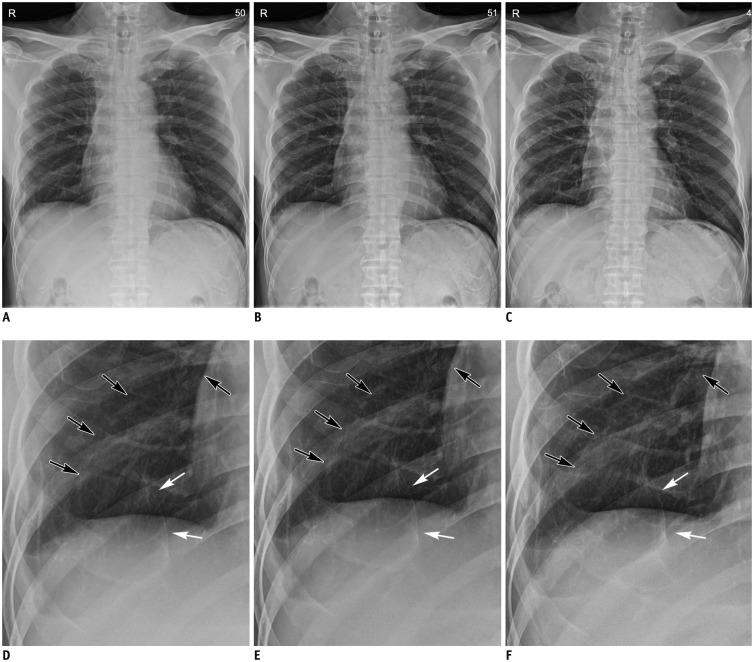

Each of the 38 patients underwent bedside chest radiography with and without a grid. A grid-like image was generated from a non-grid image using SimGrid software (Samsung Electronics Co. Ltd.) employing deep-learning-based scatter correction technology. Two readers recorded the preference for 10 anatomic landmarks and the overall appearance on a five-point scale for a pair of non-grid and grid-like images, and a pair of grid-like and grid images, respectively, which were randomly presented. The dose area product (DAP) was also recorded. Wilcoxon's rank sum test was used to assess the significance of preference.

Both readers preferred grid-like images to non-grid images significantly ( < 0.001); with a significant difference in terms of the preference for grid images to grid-like images ( = 0.317, 0.034, respectively). In terms of anatomic landmarks, both readers preferred grid-like images to non-grid images ( < 0.05). No significant differences existed between grid-like and grid images except for the preference for grid images in proximal airways by two readers, and in retrocardiac lung and thoracic spine by one reader. The median DAP were 1.48 (range, 1.37-2.17) dGycm in grid images and 1.22 (range, 1.11-1.78) dGycm in grid-like images with a significant difference ( < 0.001).

The SimGrid software significantly improved the image quality of non-grid images to a level comparable to that of grid images with a relatively lower level of radiation exposure.